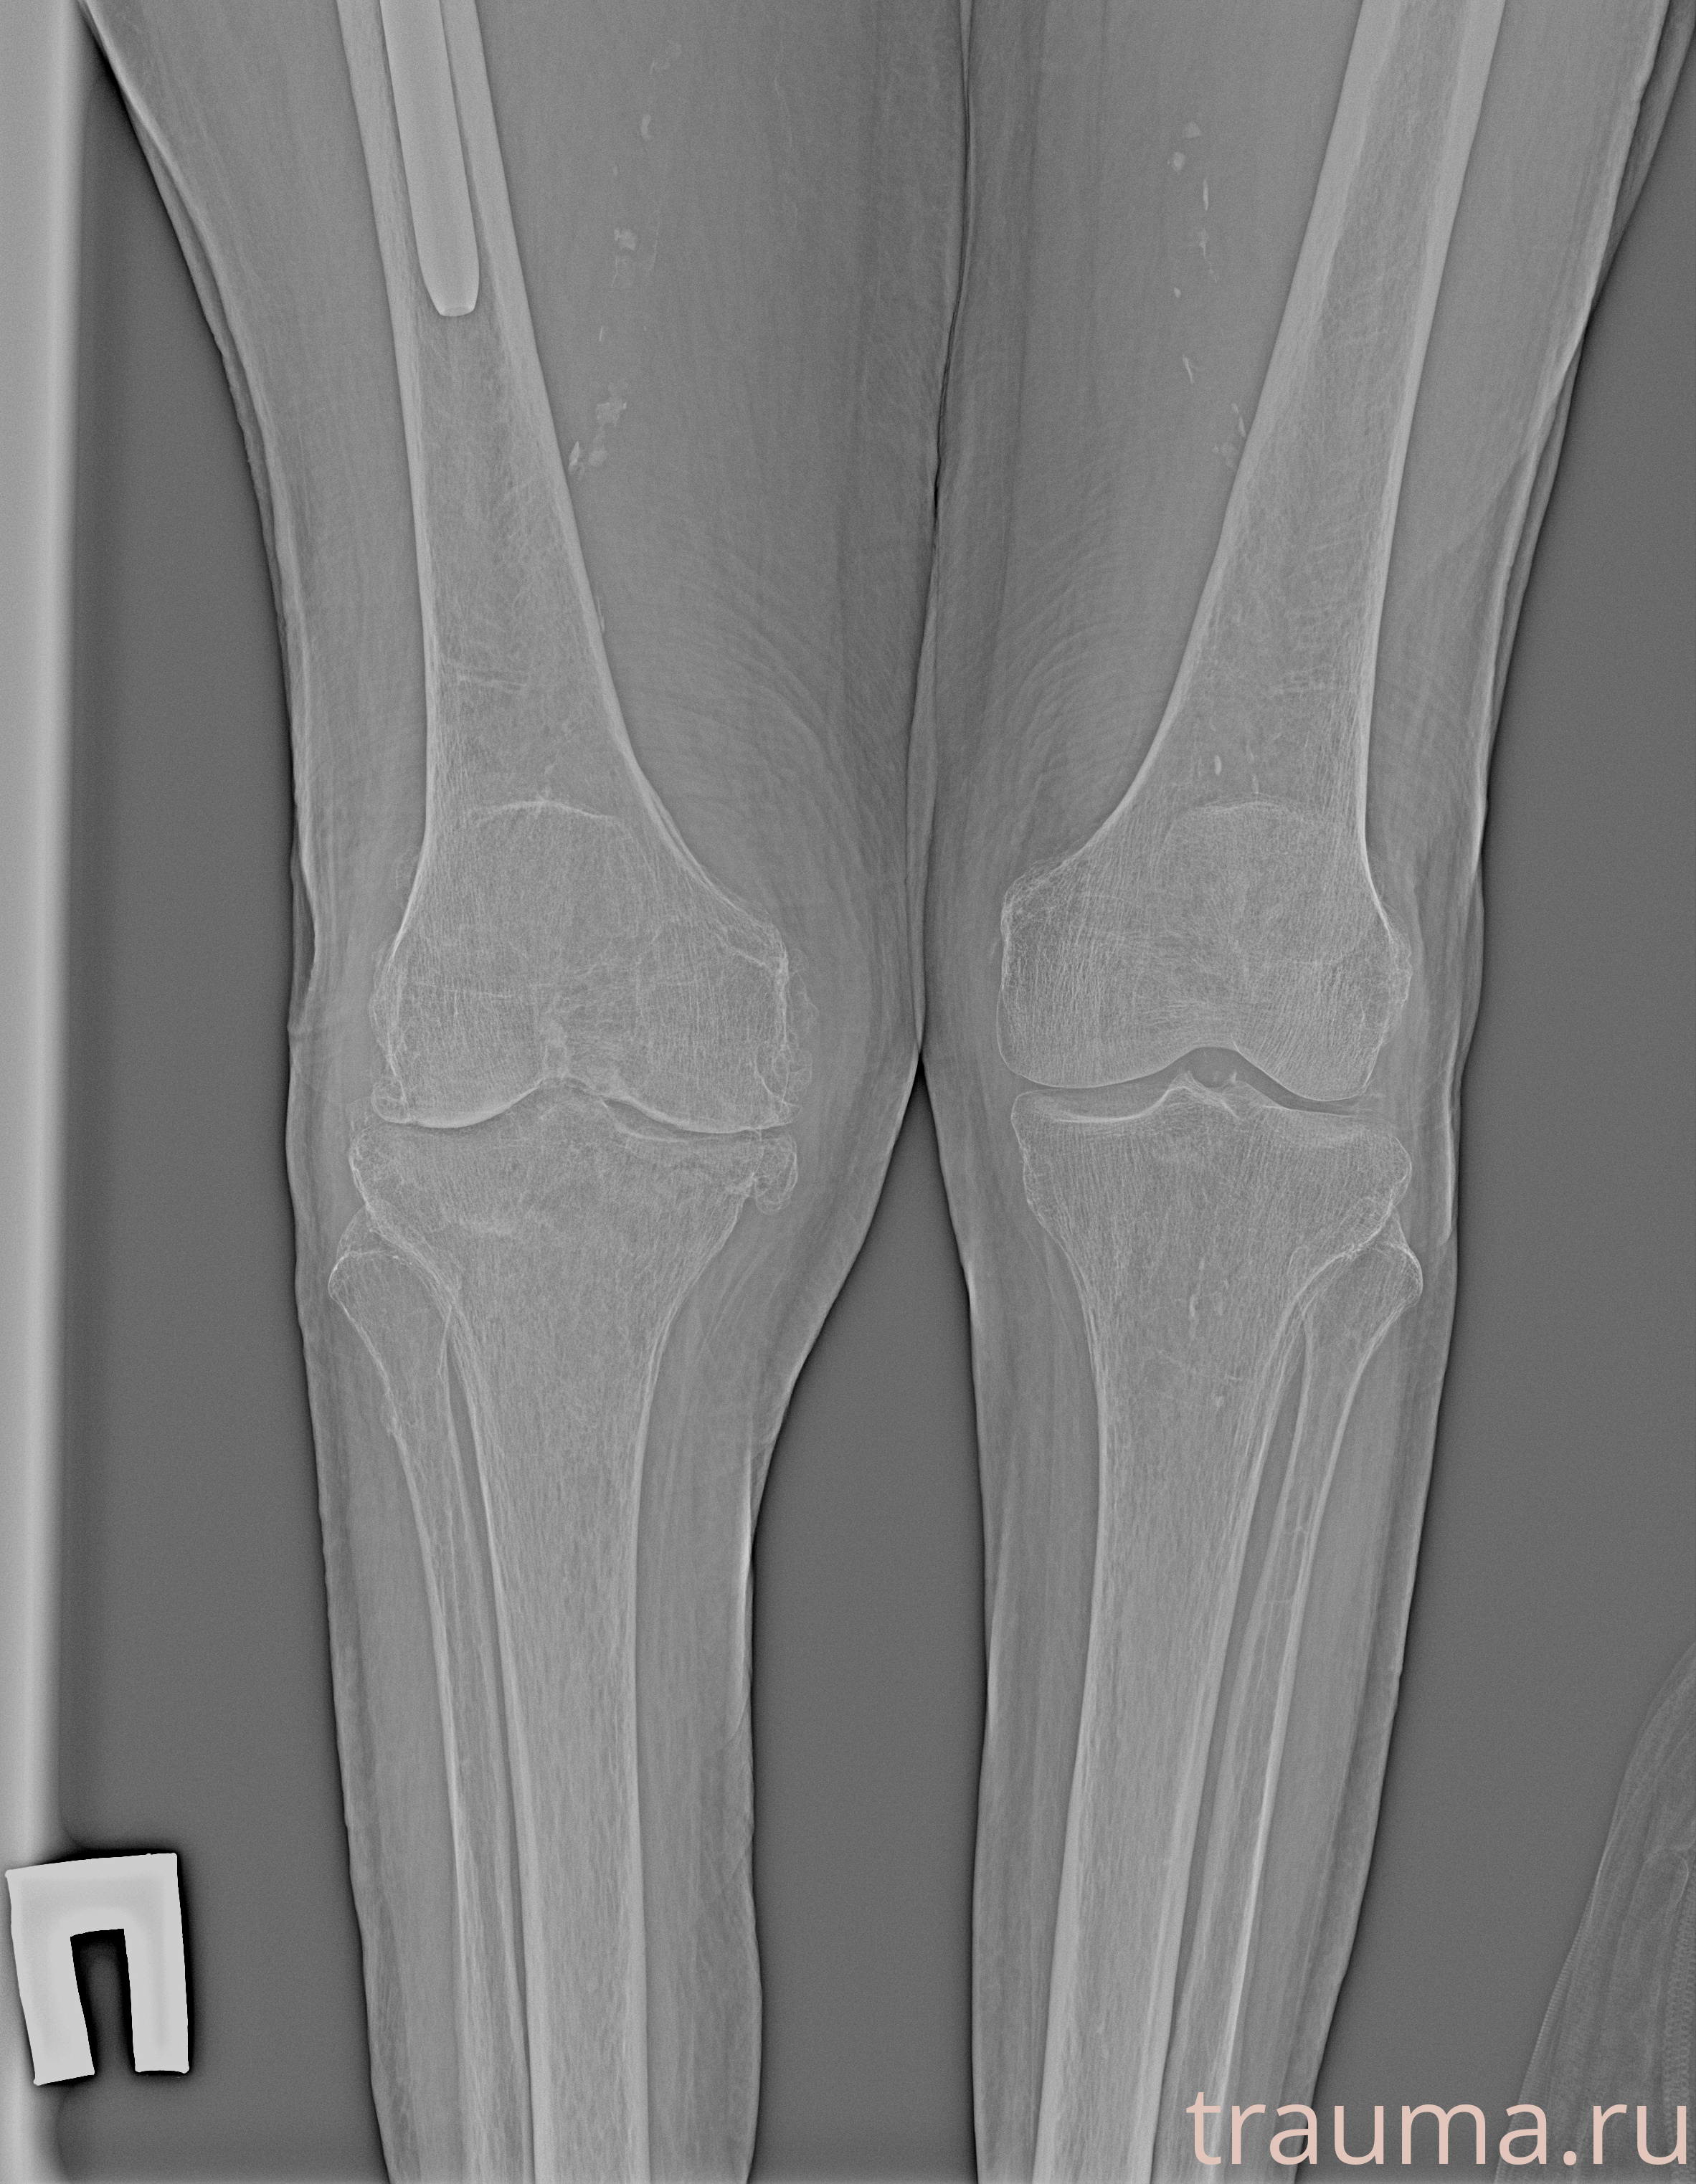

Рентгенограммы

Рентген на дому: по вашему адресу приезжает врач-рентгенолог, травматолог-ортопед с мобильным рентгеновским аппаратом, проводит диагностику травмы или заболевания, делает необходимые рентгенограммы, дает рекомендации по дальнейшему лечению. Получить качественные снимки в домашних условиях возможно благодаря уникальной методике, разработанной МосРентген Центром для института  Склифосовского